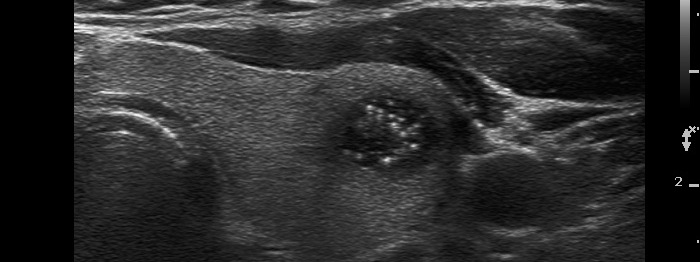

Benign cystic-colloid goiter (cytological diagnosis) - case 284 |

The figure marked with white double arrow is ambiguous because of the lack of dorsal tail. This figure is composed of two granules which might be two punctate echogenic foci. However, there are typical forms of comet-tail artifacts, the presence of which makes it very likely that the equivocal figures are also comet-tail artifacts. Moreover, these are within cystic fluid which theoretically excludes that these might be pathognomic microcalcifications. In addition to it is worth analyzing the dorsal wall of the cyst and the thyroid parenchyma dorsal to the nodule, both have hyperechogenic figures corresponding to a posterior back wall enhancement.